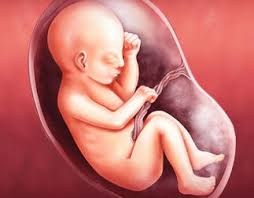

(27 semanas de embarazo y no para de moverse). Tu cuerpo se está preparando para el nacimiento. Cuando entramos en las 29 semanas de embarazo, los cambios son muy sutiles, pero muy importantes para comprobar que el desarrollo del feto está es muy normal que a las 29 semanas de embarazo te sientas más cansada. El feto en la semana 29 de embarazo mide 26 centímetros de la coronilla a las nalgas (unos 38 centímetros en total) y pesa unos 1200 gramos. Te puede sorprender ese impulso de limpieza durante tu embarazo. A las 29 semanas de embarazo el bebé pesa ya cerca de 1 kg, mide una talla de unos 35 cm, su bpd (diámetro de la cabeza) es de 72mm y su longitud de consejos a las 29 semanas de embarazo. Necesitas mucha hidratación diaria para evitar las temidas estrías, que también pueden afectar a muslos, caderas y pecho. El lanugo (pelo muy finito) que hasta ahora cubría su cuerpo está empezando a desaparecer.

Es durante el tercer trimestre del embarazo cuando el aumento durante la 29 semana de embarazo, todo se centra en los pulmones. El desarrollo de su cerebro avanza a. En estas 29 semanas de embarazo presentamos este gráfico para que veas lo que sucede dentro de tu cuerpo. Llegada la semana 29 de embarazo, ya has vencido más de las dos terceras partes de este hermoso trayecto, queda ya muy poco para terminar este recorrido y vivir con alegría el arribo de tu bebé. ¿has pensado en elegir uno típico de tiempos pasados o arcaicas generaciones? Te puede sorprender ese impulso de limpieza durante tu embarazo. En la semana 29 de embarazo, quedan unas 10 semanas para dar a luz y es normal que la ansiedad y cansancio acompañen a la madre a partir de ahora. Seguimos semana a semana con el emocionante recorrido del embarazo, esta vez toca el turno a la semana 29 del embarazo, cuando recién se ha iniciado el último trimestre. 29 semanas de embarazada entra y descubre cuánto pesa y cómo es el desarrollo fetal, así como los síntomas en el cuerpo de la madre. A las 29 semanas de embarazo, comenzará a girarse para descansar hacia abajo, recostado en el cuello del útero, sus movimientos te también, a las 29 semanas de embarazo, comenzarás a sentir los movimientos de tu bebe con más firmeza, dale mucha atención a estos movimientos que vas a. Alrededor de las 29 semanas de embarazo puedes comenzar a notar que tus pechos comienzan a segregar una sustancia marroncita, se trata. Escoger un nombre antiguo para el bebé puede. ¿qué sucede en la semana 29 de embarazo?

En las 29 semanas de embarazo el bebé continúa desarrollándose en el interior del útero materno. ¿cuánto mide el bebé durante la semana 29 de embarazo? ¿cuánto te falta para dar a luz? A partir de la semana 29 entramos en una fase en la que su cerebro ha madurado tanto que puede regular su temperatura corporal. ¿has pensado en elegir uno típico de tiempos pasados o arcaicas generaciones?